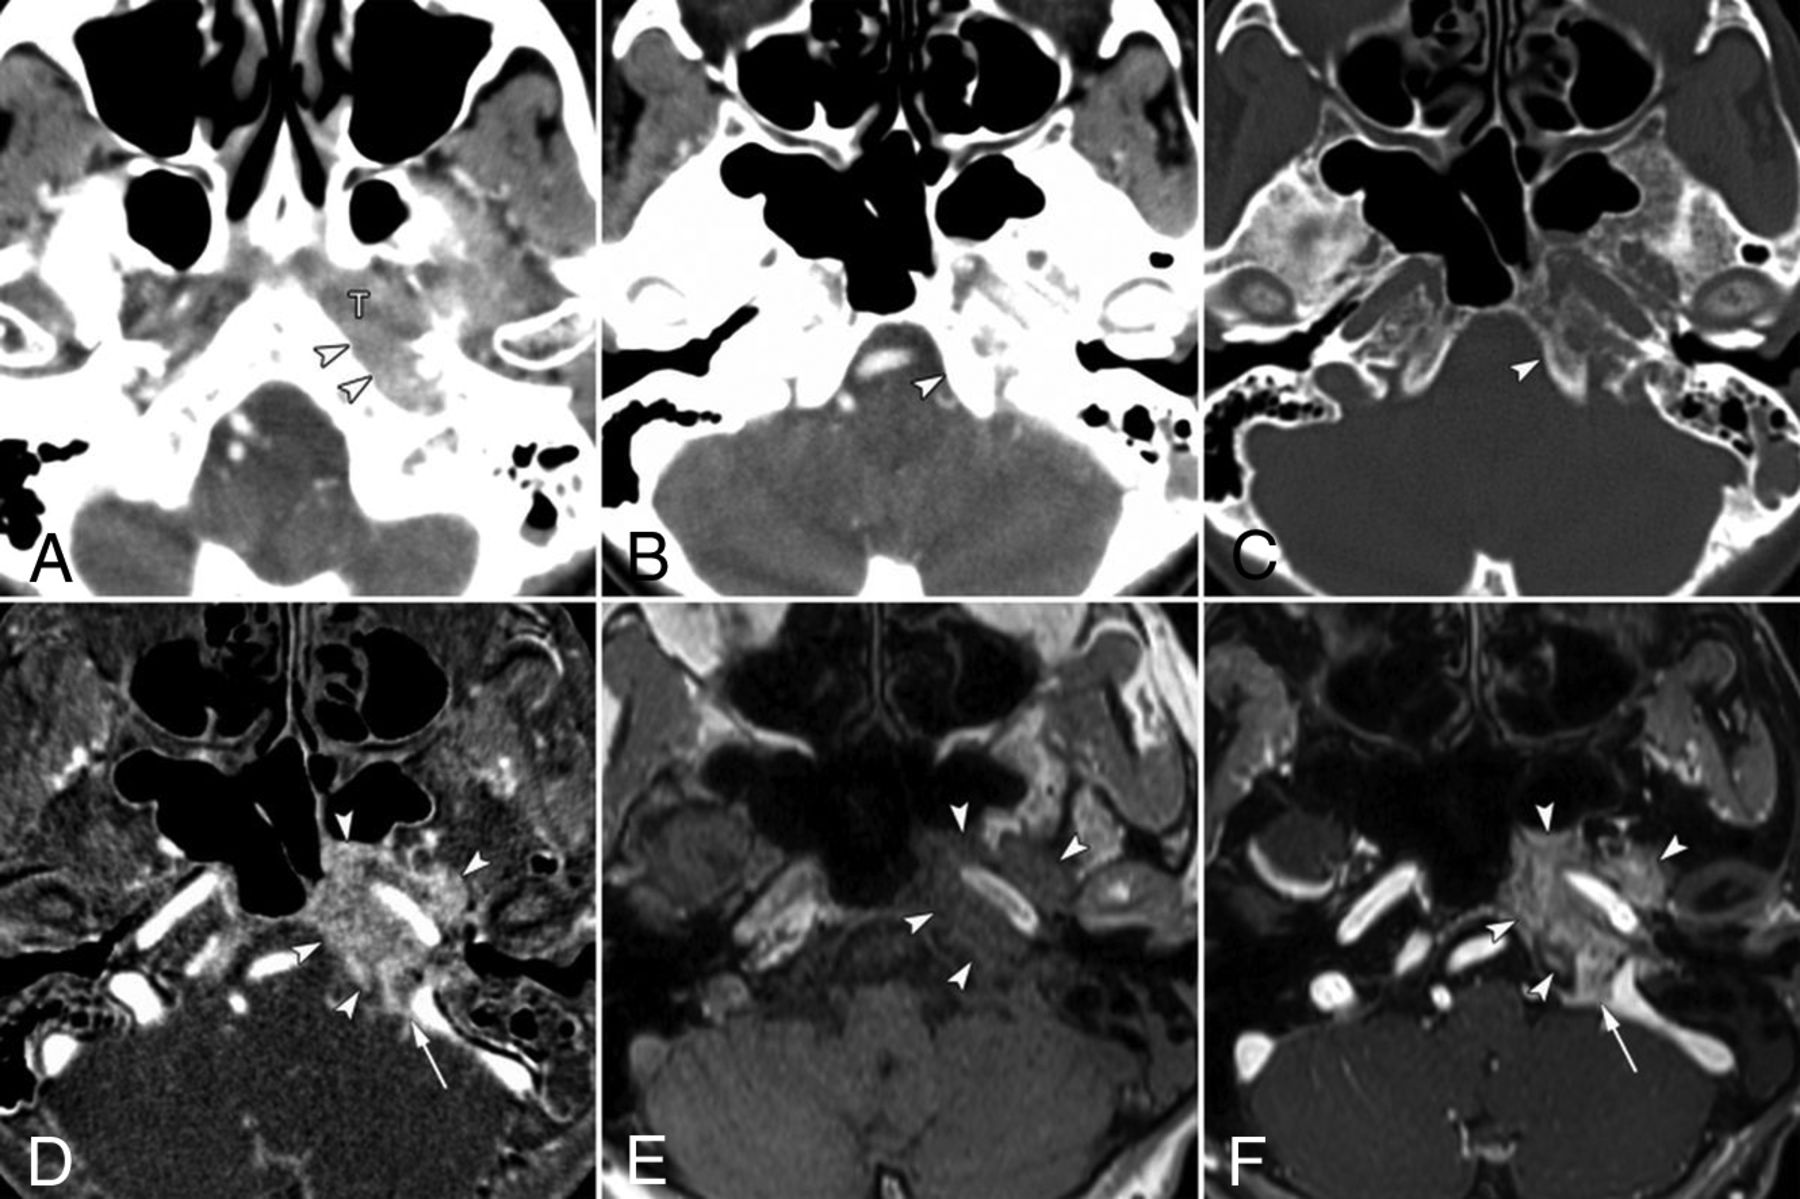

False-negative findings for skull base invasion by conventional CT images alone in a 74-year-old woman with nasopharyngeal carcinoma. A, Axial contrast-enhanced CCT image (soft-tissue window) shows nasopharyngeal tumor (T) spread into the lateral soft tissue around the foramen lacerum (arrowheads). CCT images at the skull base level (B, soft-tissue window; C, bone window) show no destruction of the skull base at the clivus (arrowhead). D, Bone subtraction iodine image shows remarkable skull base invasion into the bone marrow space such as the clivus, petrous apex, and sphenoid bone (arrowheads) with intracranial extension at the jugular foramen (arrow). A corresponding slice on a T1-weighted image (E) and fat-suppressed T1-weighted image after gadolinium administration (F) show tumor invading the clivus (arrowheads) and spread into the jugular foramen (arrow).